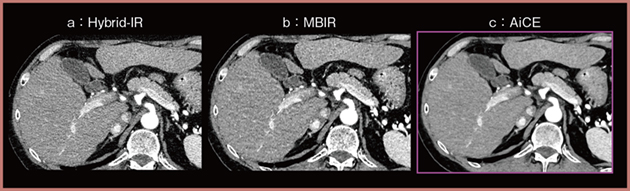

図1は肝臓のダイナミックCT動脈相の画像であるが,Hybrid-IR(a),MBIR(b)と比較して,AiCE(c)ではノイズが良好に低減しており,臨床に耐えうる画質が得られている3)。

図1 腹部高精細CTにおけるAiCEによる画質向上3)